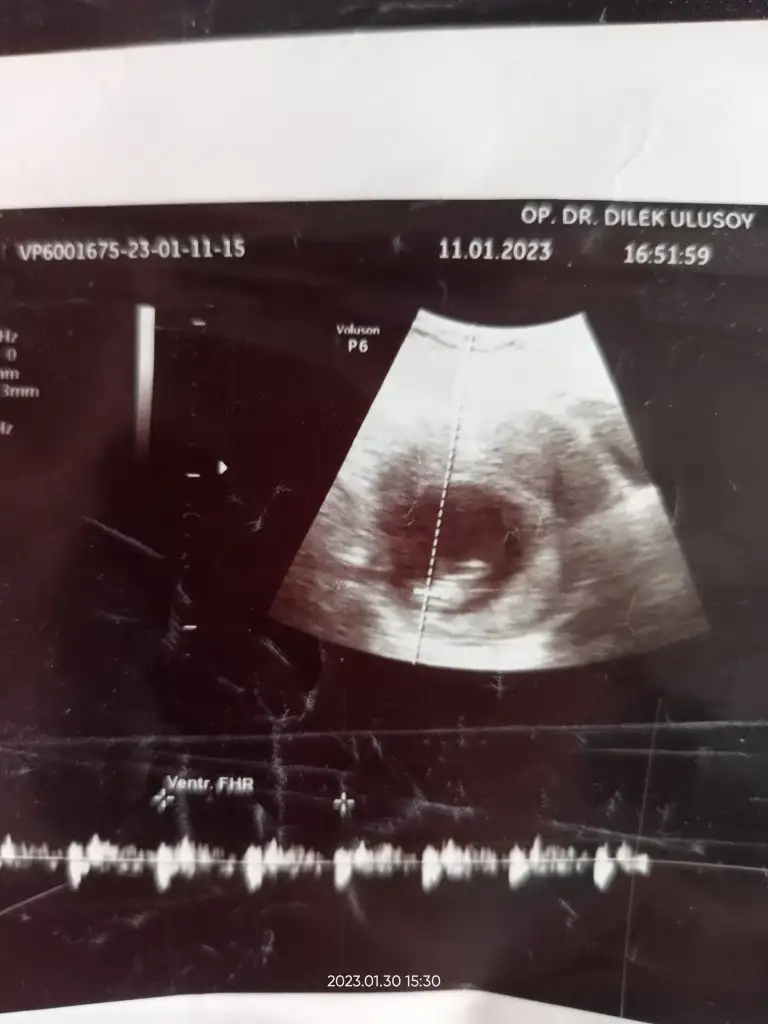

Merhaba 11e 4 haftalık cinsiyeti nedir yorumunuzu bekliyorum.

• IMG-20230111-WA0002.webp

IMG-20230111-WA0002.webp

18,7 KB · Görüntüleme: 81